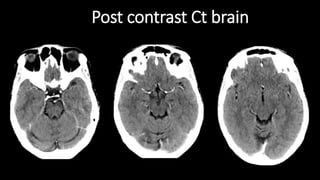

Post contrast Ct brain